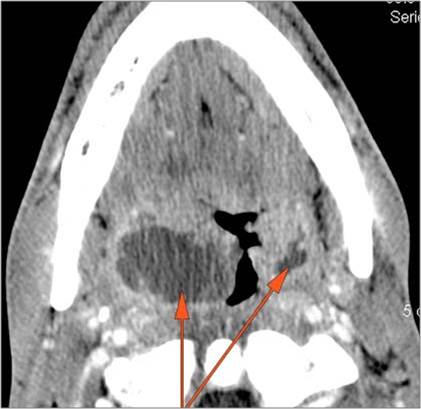

Cervical Lymph Nodes

If there is suppurative cervical adenopathy the purulent material outside the lymph node(s) capsule(s).

Vascular Findings